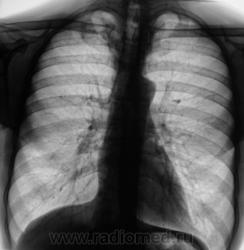

Взяли на контроль.  Какие мнения будут по поводу наличия/отсутствия специфического процесса.

Произвели стандартное дообследование.